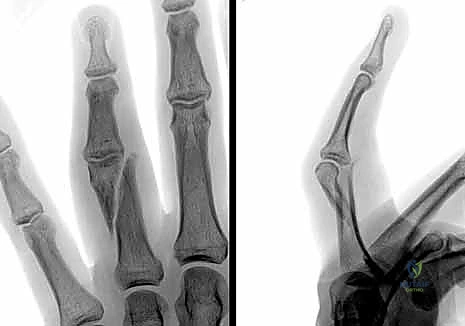

- تشوه مرئي في الإصبع: قد يبدو الإصبع أقصر من الطبيعي، أو منحنياً بزاوية غير طبيعية، أو ملتفاً حول محوره (Malrotation).

- ظاهرة تداخل الأصابع (Scissoring): وهي من أهم العلامات السريرية التي يبحث عنها د. هطيف. عند محاولة المريض إغلاق يده (صنع قبضة)، يتقاطع الإصبع المكسور فوق أو تحت الإصبع المجاور بدلاً من أن يشير بشكل متوازي نحو العظم الزورقي في المعصم. هذا يدل على وجود تشوه دوراني يجب تصحيحه جراحياً.

- التصوير بالأشعة السينية (X-rays): هو المعيار الذهبي لتشخيص كسور السلاميات. يطلب الدكتور هطيف دائماً ثلاث وضعيات أساسية:

- الأمامية الخلفية (AP View).

- الجانبية الحقيقية (True Lateral View): وهي الأهم لتقييم مقدار الانزياح الزاوي.

- المائلة (Oblique View): تساعد في رؤية الكسور الشعرية الدقيقة أو الكسور المفصلية الخفية.